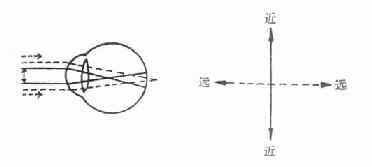

图16-9 单纯近视散光

图16-10 单纯远视散光

图16-11 复性近视散光

2.复性散光:两条主经线的屈光力不同,且都是远视性的(复性远视散光)或近视性的(复性近视散光)。

图16-12 复性远视散光

3.混合性散光:一条主经线为远视,另一条主经线为近视。

图16-13 混合性散光